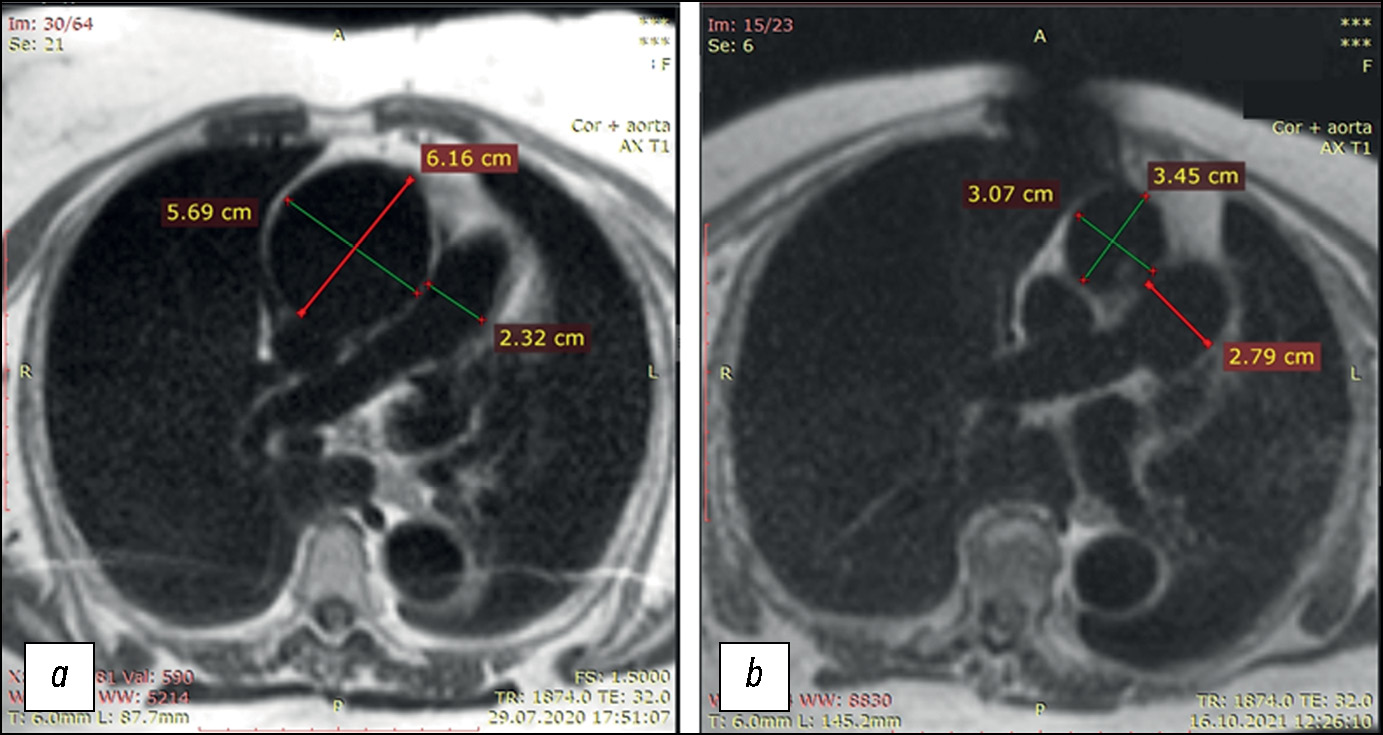

Comparison of the diagnostic accuracy of whole-body diffusion-weighted imaging and 18F-prostate-specific membrane antigen-1007 positron emission tomography combined with computed tomography for detecting bone metastases in prostate cancer

Abstract

BACKGROUND: The increasing availability of 18F-prostate-specific membrane antigen-1007 (18F-PSMA-1007) for prostate cancer staging highlighted its advantages, particularly its higher spatial resolution compared to analogs. Moreover, accumulating scientific data indicate an increase in false-positive findings, predominantly in bones, which may lead to unwarranted upstaging of the disease. Diffusion-weighted imaging may be used for the early detection of bone metastases.

AIM: This study aimed to assess and compare the diagnostic accuracy of whole-body 18F-PSMA-1007 positron emission tomography combined with computed tomography and whole-body and pelvic bone diffusion-weighted imaging in patients with prostate cancer.

METHODS: A retrospective single-center selective study was conducted. The imaging results of 119 patients with prostate cancer were divided into two groups: group 1 comprised 40 pairs of 18F-PSMA-1007 positron emission tomography combined with computed tomography and whole-body diffusion-weighted magnetic resonance imaging scans, and group 2 included 79 pairs of similar studies, with magnetic resonance imaging performed only for the pelvic bones. The diagnostic studies were performed at an inter-study interval ≤14 days. The metastatic bone lesions detected in different anatomical regions was counted using data from 18F-PSMA-1007 positron emission tomography combined with computed tomography and magnetic resonance imaging. Lesions were considered true positives if confirmed by additional magnetic resonance imaging pulse sequences and/or follow-up observation.

RESULTS: Whole-body diffusion-weighted imaging demonstrated higher specificity (58.1%) for detecting bone metastases than 18F-PSMA-1007 positron emission tomography combined with computed tomography (51.06%). However, its sensitivity was lower: 93.22% versus 97.55%.

CONCLUSION: Despite its advantages, 18F-PSMA-1007 positron emission tomography combined with computed tomography shows a high rate of false-positive bone findings. These are most commonly noted in the ribs, vertebrae, and pelvic bones. Suspicious bone lesions should be further evaluated to avoid unjustified disease upstaging. Thus, whole-body magnetic resonance imaging with diffusion-weighted sequences and selective fat signal suppression can be used.